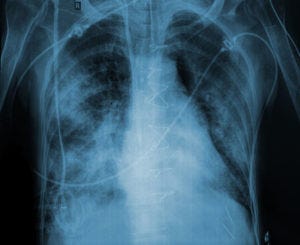

Extracorporeal membrane oxygenation (ECMO) is an accepted salvage therapy for severe acute respiratory distress syndrome (ARDS) after conventional mechanical ventilation with low tidal volumes, neuromuscular blockade and prone positioning have failed. ECMO has been proposed as the ultimate lung protection strategy for ARDS, because it bypasses the lungs entirely. So why shouldn't it be first-line therapy for ARDS? A recent trial conducted in France asked that question.

Investigators randomized 240 patients to receive veno-venous ECMO or usual ARDS care within 7 days of intubation. At enrollment, all patients received low tidal volume ventilation, almost all had received neuromuscular blockers, and most had been proned. 60-day mortality was the primary endpoint.